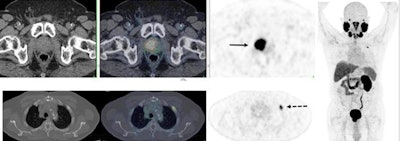

PET/CT imaging with an F-18 DCFPyL prostate-specific membrane antigen (PSMA) radiopharmaceutical changed prostate cancer management in two-thirds of cases, according to research presented July 13 at the Society of Nuclear Medicine and Molecular Imaging (SNMMI) 2020 virtual annual meeting.

Previous research has suggested that PSMA-PET/CT is effective for diagnosing prostate cancer, but its impact on management of patients with suspected recurrent disease has been unclear, wrote a team led by Dr. Ur Metser of the University of Toronto in Canada. To address the question, the group conducted a study using PSMA-PET/CT that included 410 men with suspected recurrent cancer who had no disease on conventional CT or bone scintigraphy and who had undergone multiple prostate cancer treatments.

Of the 410 men, 64% had PET-detected lesions. In all, 56% of men with negative conventional imaging results had lesions detected by PET; among those with lesions on conventional imaging, 63% were found to have new ones. PET/CT imaging also showed the following:

PSMA-PET/CT altered treatment in 66% of the men, the most common shifts being from observation or systemic therapy to surgery or radiation.